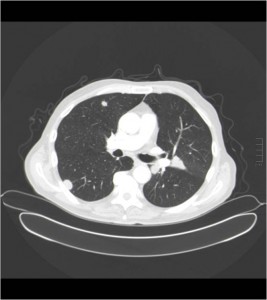

La elección más adecuada es la “C ”, TC torácico y abdominopélvico con contraste oral e intravenoso, debido a que ante una colonoscopia informada de tumor de colon para valorar el estudio de extensión, a distancia con tc de tórax o invasión locorregional a otros órganos vecinos, infiltración ganglionar, nódulos en peritoneo o hepáticos con el tc abdominopélvico.

HALLAZGOS: